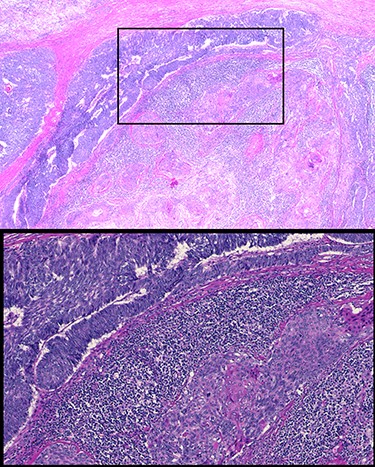

Patient underwent resection of the mediastinal mass. A median sternotomy was performed in typical fashion. Dissection was carried out along the innominate vein where significant desmoplastic reaction from the tumor was present. Upon entry into left chest, the tumor was noted to have contiguous spread into the left upper lobe that unfortunately involved a substantial portion of the phrenic nerve. Decision was made to divide the left phrenic nerve and resect a wedge of left upper lobe en bloc with the tumor. Final pathology report described a 10.2 × 7.5 × 6.0 cm tumor with histology consistent with basaloid carcinoma of thymic gland, with involvement of pulmonary parenchyma and presence of lympho-vascular invasion (Fig. 3). All margins were negative with closest margin being 3 mm. Final pathological stage was pT3N0M0.

Histology of resected thymic gland with enlarged inset showing palisading and squamous features highly suggestive of basaloid carcinoma.